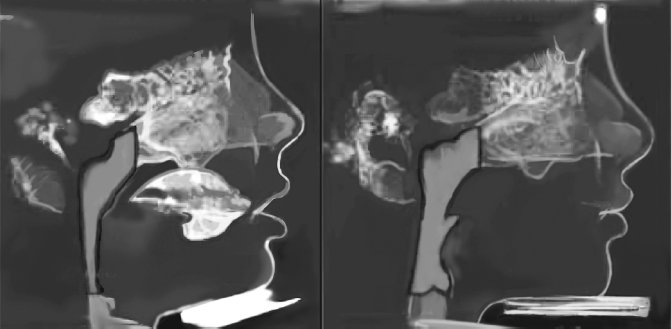

![]() Рисунок 6. Результаты лечения, проведенного ортодонтом Джоном Мью (фотографии любезно предоставлены Джоном Мью) Итак, суть всего, что было сказано, в следующем: ваше здоровье и счастье, а также, скорее всего, здоровье и счастье ваших детей, могут находиться под угрозой из-за привычек, о которых большинство из нас и вовсе никогда не задумывается. Вот несколько ключевых вопросов, которые вы можете задать самому себе. • Соприкасаются ли обычно зубы верхней и нижней челюсти? Дышите ли вы ртом или носом? • Просыпаетесь ли вы по ночам? • Жалуется ли ваш партнер на то, что вы храпите? • Сколько раз ваш ребенок пережевывает каждую порцию еды? • Полезно ли прикармливать младенца специальным детским питанием? • У вашего ребенка постоянно заложен нос? • Глотает ли ваш ребенок еду со странным выражением лица? • Спит ли он с открытым ртом? • Ворочается ли он во сне, комкая постельное белье? • Часто ли он бывает уставшим? То, как мы едим, может быть не менее важным, чем то, что мы едим. То, как мы дышим, может быть не менее значимым, чем качество воздуха. То, как мы спим, может быть не менее серьезным вопросом, чем продолжительность сна. Все это – важнейшие составляющие нашего здоровья, связанные с лицом и челюстью. Все эти зловещие предостережения уже начинают напоминать вам советы по правильному питанию, которые вы читали прежде? Когда продукты, которых еще вчера вас убеждали избегать, по результатам «новых исследований» оказывались абсолютно безвредными? Сначала говорят, будто жиры полезны, потом они оказываются вредны, а теперь снова считаются необходимыми. Кофе то вредно, то полезно, то снова становится запретным продуктом. Глютен вреден, витамин Е полезен, и так далее. Информация и предписания, представленные в этой книге, могут показаться вам очередными причудливыми и бесполезными советами, однако это не так. Часть данных в книге известна уже достаточно давно, а некоторые простые рекомендации могут напомнить вам нравоучения вашей матери, которая раз за разом повторяла, чтобы вы ели с закрытым ртом, не сутулились и хорошо пережёвывали еду. Что ж, она была права. Возможно, она этого и не осознавала, однако ее требования касались не только хороших манер и вежливого поведения – это была одна из мер по предотвращению тенденции, которая теперь стала серьезнейшей проблемой общественного здравоохранения. Челюстно-лицевая эпидемия развивалась веками, однако ее распространение значительно ускорилось из-за образа жизни, характерного для индустриальной западной цивилизации, который после Второй мировой войны буквально захватил мир. Как следствие, вы не найдете в этой книге никаких простых и быстрых решений – здесь подробно рассматривается эта сложная проблема и представлены рекомендации по ее предотвращению и лечению, а читателю дается пища для размышления. ![]() Рисунок 7. Расширение дыхательных путей у мальчика после ортотропического лечения и исправления осанки лица. Подобный эффект продемонстрирован на шестом рисунке Можно перефразировать известное выражение, и сказать, что лицо – зеркало души, однако оно является еще и отражением состояния здоровья. На лице человека можно разглядеть потенциальные признаки серьезных нарушений. Вместе с тем, проблемы с челюстью и черепом не только могут быть индикатором патологий – они также могут определять степень вашей привлекательности. А привычки, из-за которых лицо может стать с точки зрения нашего общества некрасивым, к сожалению, также могут привести и к различным болезням. Таким образом, мы сами не заметили, какие перемены произошли в нашем обществе. Мы меняем свои лица с помощью операций, брекетов и других технических средств, в то время как на самом деле следует изменить то, как мы обычно дышим, едим и спим. Так мы сможем улучшить внешний вид и здоровье значительно сильнее, и эффект продлится дольше, чем после пластической операции. Стремление быстро решить проблемы со здоровьем и улучшить улыбку в некоторых случаях со временем приводит лишь к дополнительным проблемам. На лице человека можно разглядеть потенциальные признаки серьезных нарушений. Эта книга начинается с главы, описывающей переход от здоровой челюсти каменного века к зачастую болезненной современной – наглядный пример культурной эволюции (изменения ненаследственной информации, которой владеют группы людей). В ней рассматривается давний вопрос соотношения генетики и среды применительно к изменениям, произошедшим с челюстью и лицом. Вторая глава посвящена главным образом процессу жевания, однако затрагивает и другие факторы, такие как аллергии, тесно связанные с челюстной эпидемией. В третьей главе речь пойдет о значении того, что и как мы жуем, а также где мы едим. В четвертой главе мы обсудим связь привлекательности и здоровья челюсти. В пятой расскажем о том, как и почему у человека меняются челюсть, лицо и его осанка. Шестая глава сосредоточена на ротовом дыхании и связанных с ним проблемах. В седьмой главе объясним, какие меры вы и ваша семья можете предпринять, чтобы сдержать эту эпидемию. В восьмой главе мы поговорим о том, как распознать ее последствия, а также опишем, где вы можете получить надлежащую помощь специалистов. В девятой главе поразмышляем о том, какие культурные изменения в нашем обществе могут помочь людям вроде вас справиться с этой эпидемией. ![]() Рисунок 8. Девочке слева сказали, что для исправления ее опущенного подбородка необходима операция. Ортотропическое лечение с помощью системы Biobloc и упражнений по исправлению осанки лица привели к поразительным результатам, которые можно увидеть на правой фотографии. Ни ортодонтия, ни ортопедия не могут гордиться такими впечатляющими изменениями челюсти (Фотографии любезно предоставлены Джоном Мью) Будучи учеными, на страницах этой книги мы ссылаемся на научные труды, описывающие развитие челюсти, культурные традиции, различные условия дыхания и употребления пищи, а также связанные с ними проблемы со здоровьем и внешностью. Как это часто бывает при содействии естественных и гуманитарных наук, данная литература, к сожалению, содержит по большей части обрывочные знания. Отчасти это связано с этическими ограничениями по проведению контролируемых наблюдений или (особенно, как уже говорилось, в случае с апноэ во сне) экспериментов над людьми. Кроме того, проведение так называемых проспективных исследований – исследований, участников которых подбирают заранее с целью дальнейшего наблюдения – требует большой организационной работы и, что самое важное, щедрого финансирования. Это золотой стандарт изучения здоровья отдельных популяций. Чтобы сотни людей, несмотря на неудобства, действовали определенным образом (например, в течение длительного времени соблюдали особую диету), вели подробные записи и регулярно отвечали на вопросы исследователей, необходимо приложить много усилий и потратить немало денег. Проспективные исследования требуют огромных затрат и не меньшего терпения и могут тянуться годами. |